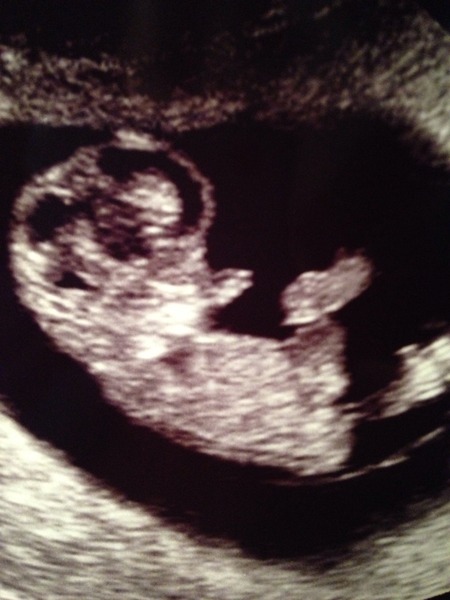

Just popping on v quickly to say thank you for the good wishes - they worked! Here's baby baguettes at 10 weeks. We got waves and kicks.

Hope everyone is ok xx

Had early scan, due date revised to February 20, everything looks great, got to see a nice strong heartbeat. Not-so-secretly hoping this is a Leap Day baby (women in my family always go to 41-44 weeks).